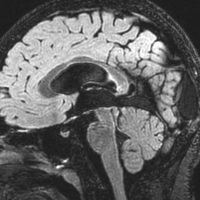

9歳男児の松果体奇形腫です。生検術と第3脳室開窓術を受けましたが,摘出術のリスクが高すぎるということで化学療法を6コース。2年間経過観察されましたが,腫瘍が増大しました。私のところへ来た時には,前後径73mmありました。

左からT2, swan, T1です。これが 類皮のう胞 dermoid cyst ということがわかります。類皮のう胞単独,あるいは成熟奇形腫の大部分としての類表皮のう胞は,かなり頻度の高いものです。松果体腫瘍で奇形腫を疑ったらまず,類皮のう胞の混在を疑います。それがあれば,かなりの確率で成熟奇形腫 mature teratomaです。

類皮のう胞は内部がほとんど皮脂,ケラチン,汗,毛髪なので,簡単に砕けるし,掻き出し吸い取ることができます。松果体成熟奇形腫の中では最も戦いやすい相手と言えるでしょう。再発しないようにするには,周囲ののう胞壁(真の腫瘍細胞)を完全摘出するしかありません。放射線も化学療法も何も効かないし,のこせば必ず再発します。

右迂回槽にちょっとdebrisは残っていますが完全摘出できました。病理は他の成分を少し混じる成熟奇形腫です。術後3年間再発はありませんし,学校へ通って体育もできています。

この手術はもちろん簡単ではありません,でもほとんどが類皮のう胞であるということがわかったので踏み込めたのです。